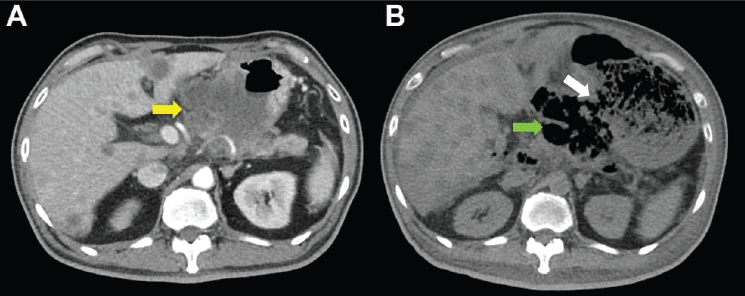

Unfortunately, a catastrophic event did happen 2 days after finishing the first course of chemotherapy. The patient experienced sudden onset of intolerable abdomen pain with hypoactive bowel sounds, muscle guarding, and definitely apparent rebounding pain. An emergent non-contrast CT scan gave a picture of distended stomach fully filled with foods, irregular mottled gas collections between stomach and duodenum, ascites accumulation, and free air in the abdomen cavity, leading to an impression of gastrointestinal tract perforation with the perforation site clearly seen (Figures 6–8). In comparison with CT scan performed at initial diagnosis, it seemed that a severe necrotising tumour lysis induced by chemotherapy, morphologically resembling emphysematous pancreatitis [14–16], could explain the whole scenario logically.

Figure 6. CT scan of the abdomen, horizontal view. A. June 8, 2019. Yellow arrow: the huge gastric tumour. B. July 3, 2019. White arrow: gastric perforation site. Green arrow: Necrotising tumour lysis simulating emphysematous pancreatitis.